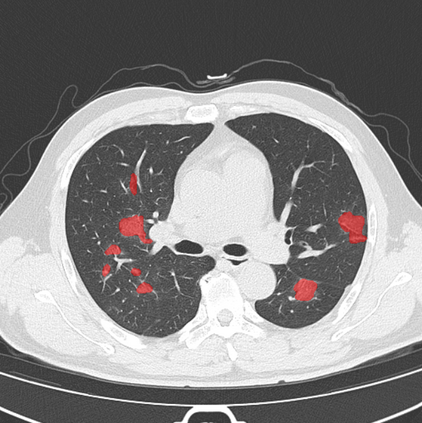

The COVID-19 pandemic has had a considerable impact on day-to-day life. Tackling the disease by providing the necessary resources to the affected is of paramount importance. However, estimation of the required resources is not a trivial task given the number of factors which determine the requirement. This issue can be addressed by predicting the probability that an infected patient requires Intensive Care Unit (ICU) support and the importance of each of the factors that influence it. Moreover, to assist the doctors in determining the patients at high risk of fatality, the probability of death is also calculated. For determining both the patient outcomes (ICU admission and death), a novel methodology is proposed by combining multi-modal features, extracted from Computed Tomography (CT) scans and Electronic Health Record (EHR) data. Deep learning models are leveraged to extract quantitative features from CT scans. These features combined with those directly read from the EHR database are fed into machine learning models to eventually output the probabilities of patient outcomes. This work demonstrates both the ability to apply a broad set of deep learning methods for general quantification of Chest CT scans and the ability to link these quantitative metrics to patient outcomes. The effectiveness of the proposed method is shown by testing it on an internally curated dataset, achieving a mean area under Receiver operating characteristic curve (AUC) of 0.77 on ICU admission prediction and a mean AUC of 0.73 on death prediction using the best performing classifiers.